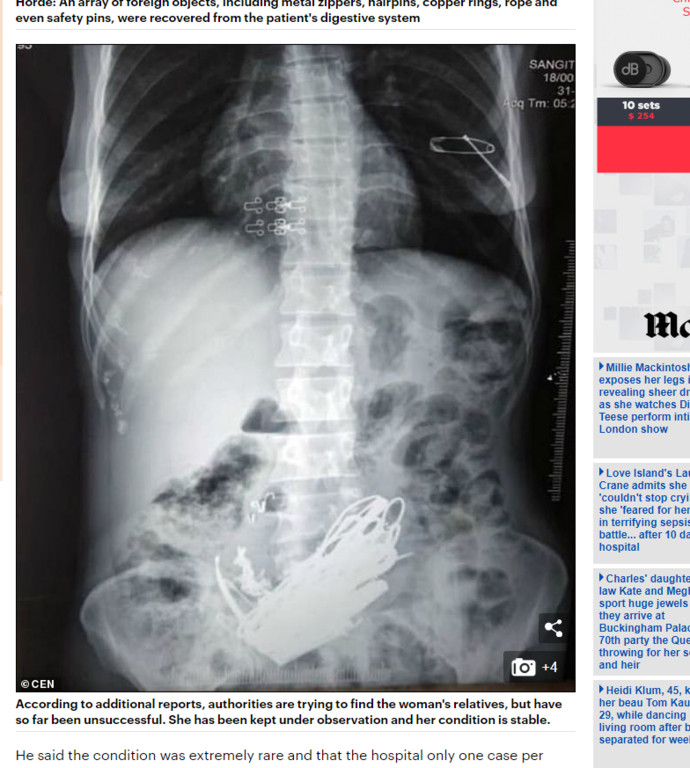

▲印度女的腹部X光裡看的到超多異物。(圖/翻攝自每日郵報)

印度一名40幾歲女性在上個月因為腹痛就醫,隨後被安排住院,不過醫生卻從該名患者的X光片中,發現她的肚中滿滿都是「尖銳的金屬物品」,造成她的未變的十分堅硬,她的肺部還有一個安全別針突出的形狀。醫生表示,這名女性應該是患有罕見的心理疾病「異食癖(又稱異食症、亂食症)」,這種病例相當少見,一年大概只會出現一個。

根據外媒報導,這名女子來自印度的馬哈拉施特拉邦,她在上周就一後就一直說自己的肚子非常不舒服,照了X光後發現,她的腹中竟藏有螺栓、珠寶、金屬拉鍊、髮夾、銅環甚至是安全別針等金屬物品,醫生一共花了3個小時的時間,才從她的肚中取出大約3傍(約1.5公斤)的所有物品。

幫女子動手術的外科醫生帕馬爾(Nitin Parmar)表示,患者的胃部變的十分堅硬,X光片顯示胃的部分有一個大硬塊,還有一個安全別針從她的肺部突出來,一根針甚至刺破她的胃壁,所以促使我們要立即對她動手術。